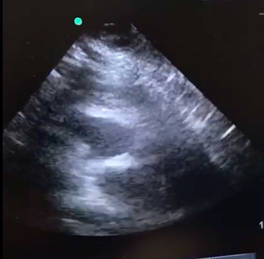

As the patient improved with hydration, the decision is made to release him. After this, the patient’s upper extremities begin to move rigidly, and his eyes deviate to the left side. The patient then states he feels dizzy and weak overall, he looks pale and then presents persistent hypotension, extreme bradycardia, distal coldness and desaturation. Ultrasound tracing of the subxiphoid window was performed with ultrasound imaging within the ventricles. Thrombolysis is begun using a recombinant tissue plasmogen activator 100mg IV over 2hours. After this is started, the patient goes into pulseless electrical activity cardiac arrest. Cerebral pulmonary reanimation maneuvers are performed. Bicarbonate (7 direct ampoules) is used, and the dose of the recombinant tissue plasmogen activator thrombolytic agent changed to 50mg via bolus. After 35minutes of reanimation, the patient regains spontaneous circulation with a sinus rhythm and hemodynamic instability. Perfusion is begun with 10 mcg/min of Adrenaline and 20mcg/kg/min of Dobutamine. Assisted mechanical ventilation is continued without sedation and analgesia. He is transferred for an angiotomography of the pulmonary vessels where acute thrombi are identified in the main pulmonary arteries on both sides and in the segmental branches in the upper and lower lobes.

Figure 1A Alterations in the size of the right ventricle, decreasing compared to the left ventricle.

Figure 1B Deviated septum.

During emergency care for this patient no CT confirmation could be performed due to rapid clinical instability, the need to secure his airways, and the early start of reanimation maneuvers. For this reason, a bedside ultrasound is performed on the patient, seeking signs of pulmonary embolism, including free intracavitary thrombi or thrombi in the pulmonary artery (as presented in this patient), or indirect signs like dilation of the Right Ventricle vs the Left Ventricle (>1:1 RV/LV), systolic disfunction of the right ventricle, septum displacement in the left ventricle, inferior vena cava (IVC) without collapse, or evidence of DVT in the lower extremities17–19 McConnell’s sign is the most sensitive and specific indirect sign: hypokinetic free wall of the right ventricle in the four-chamber projection; with an original described sensitivity of 77% and a specificity of 94%, although there are other studies that speak of a low specificity of 33 to 40%.20